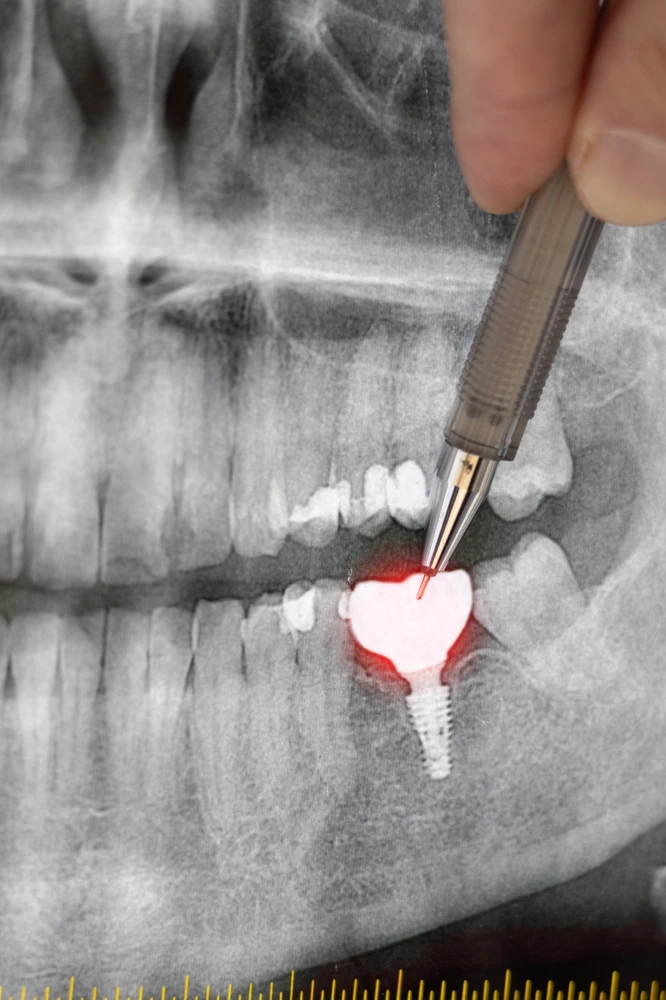

A dental X-ray showing a dental implant procedure performed at Clearly Dental Camden

The dental implant procedure involves several stages that allow the implant to integrate with the jawbone and support a replacement tooth. While the process takes time, the result is a strong and stable tooth replacement.

The first step is a consultation at Clearly Dental Camden. During this visit, the dentist examines your teeth, gums, and jawbone. X-rays or scans may be used to assess the area and plan the dental implant treatment.